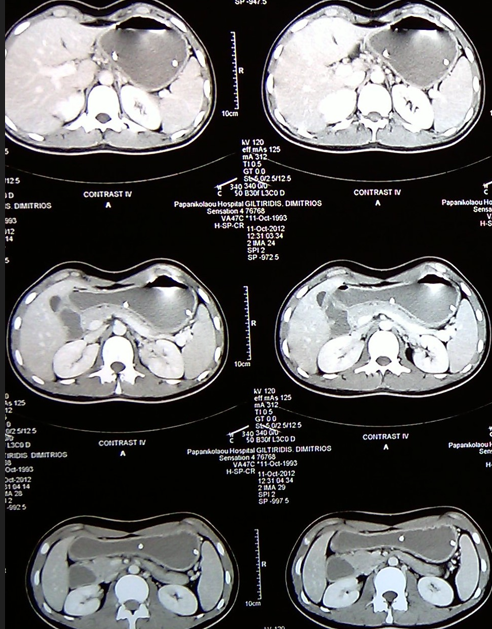

Multiple hepatic metastases — Absolute contraindication for cytoreductive surgery (Courtesy Dr. V. Penopoulos)